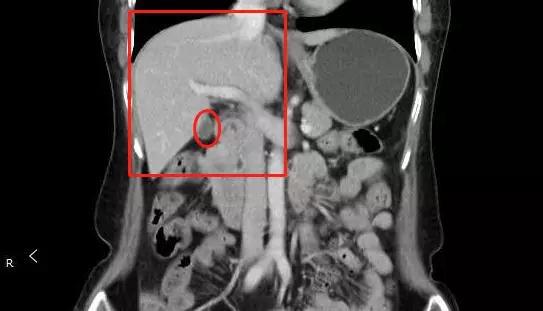

辽宁省沈阳医院泌尿生殖系统病症病历肾结石胆结石手术病历单图片

女子胸痛2周,以为胆结石,直到确诊肺癌晚期患者 我才30岁啊